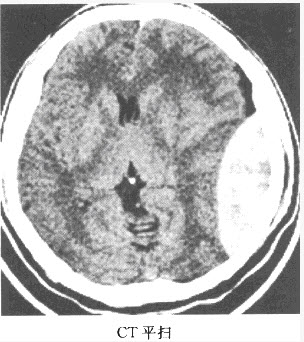

患者,男,42岁,外伤后不省人事,2小时后清醒,后又昏迷,急诊来院。

第1题,共2个问题

(单选题)患者的CT检查如下图,该患者的诊断是()

A:硬膜下血肿

B:蛛网膜下腔出血

C:硬膜外血肿

D:弥漫性轴索损伤

E:脑膜瘤

F:以上都不是

第2题,共2个问题

(单选题)该病的特点是()

A:出血可跨越颅缝

B:出血不跨越颅缝

C:出血不受颅缝影响

D:外伤后持续昏迷

E:慢性期会形成"盔甲脑"